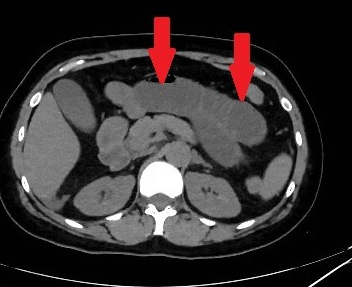

Mesenteric root infiltration — Absolute contraindication for cytoreductive surgery (Courtesy Dr. V. Penopoulos)